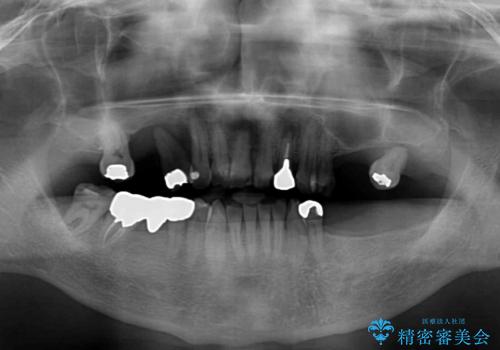

欠損の多い奥歯 インプラントによる補綴治療

- 地元ではなかなかインプラント治療を行ってくださる医院がないとのことで、転勤で東京にいる期間に治療を行いたいとのことで来院された患者様です。

上顎は左右ともに骨が少ない状態であり、特殊なドリルを用いた歯槽骨の拡大や自家骨挙上などを行いながらインプラントを埋入していくこととしました。

右下の銀歯も気になるとのことで、インプラント治療と並行してオールセラミックによるブリッジ補綴治療も行うこととしました。